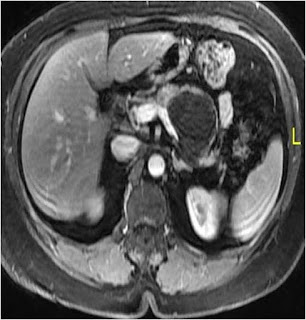

Contrast MRI with MRCP |

Cyst wall enhancing Main pancreatic duct – cyst communication absent (Figure 3) |

Figure 3. Main pancreatic duct – cyst communication absent